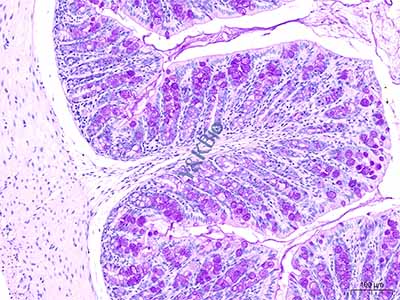

糖原是动物组织内唯一的天然多糖,广泛分布在体内各种细胞中,尤以肝脏最为丰富,对维持细胞恒定及其他生理功能有重要关系。PAS反应是显示组织、细胞内糖类物质的经典方法,PAS技术的关键是糖原被过碘酸氧化释放出醛基时,是否有足够的醛基与碱性品红发生反应。而传统切片染PAS反应显示糖原步骤繁琐,且小分子颗粒的糖原很容易在制片过程中丢失,给观察、定位、定量分析带来困难。整块染色方法具有步骤少、操作简便、反应稳定、定位清楚等特点,能减少染的切片中因固定液渗透使糖原偏居于细胞一侧的现象,而且此方法利于教学和科研大量制片和病理临床诊断。

在PAS整块染色法操作过程中一般采用固定与氧化同时进行,该方法的染色效果仍不太理想。原因是仍采用固定与氧化同时处理的方法,PAS阳性反应较弱,阳性颗粒边缘深,中间浅,颗粒分布不均匀。为解决这一问题,采用了将固定与氧化步骤分开进行的方法,结果显示PAS反应效果更好,糖原颗粒清晰,染色均匀,细胞形态结构清楚,胞核无色。此法中还发现,过碘酸氧化的时间对结果也有重要的影响,氧化时间过长,可引起非特异性反应(人工假象)。组织块整块氧化时间以24小时为佳,阳性反应强,背景淡。此外,组织块经Schiff剂染色后,一定要进行充分流水冲洗,置换组织内的Schiff剂,阻断Schiff剂与细胞内的糖原继续反应,流水冲洗至少24小时。